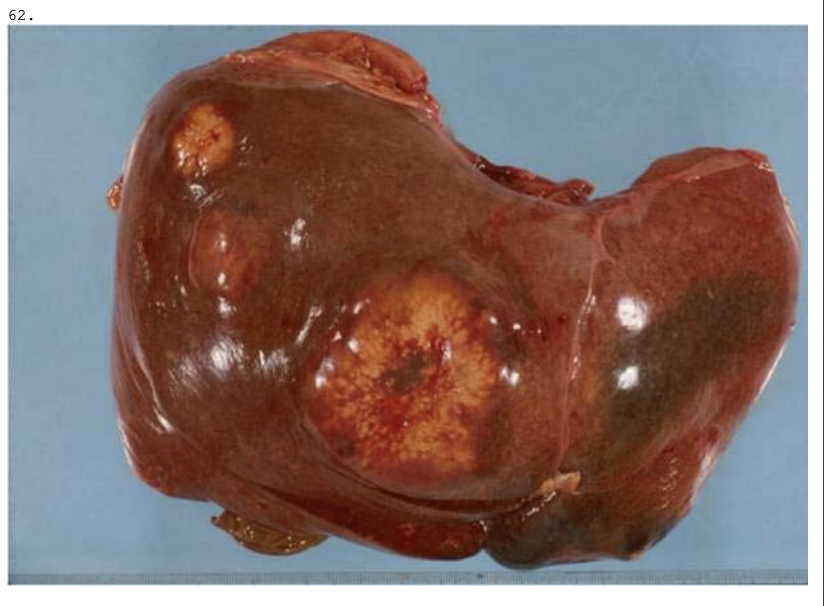

En 64-årig mand dør med symptomer på stor hjerneblødning. Ved obduktion ses forandringer i leveren som vist på billedet. Hvilken af nedennævnte diagnoser er den sandsynligste?

a. Metastaser fra pancreastumor

b. Levercirrose

c. Benigne levertumorer

d. Metastaser fra hjernetumor

e. Primær levercancer

*a. Metastaser fra pancreastumor